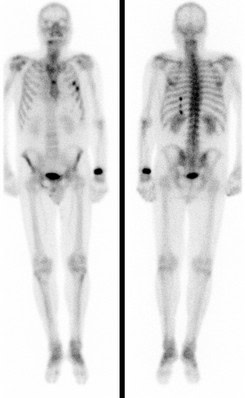

Bei der Skelettszintigraphie werden schwach radioaktiv markierte Phosphatkomplexe verabreicht, die zunächst im Blut durch den Körper zirkulieren und im Verlauf von 2-3 Stunden ausreichend in den Knochen eingebaut werden, so dass dann der Knochenstoffwechsel abgebildet werden kann.

Es bestehen die Möglichkeiten, gleich nach Verabreichung der Phosphatkomplexe die Durchblutung zu untersuchen und auf den Spätaufnahmen den Knochenumbau zu beurteilen. Bei der Skelettszintigraphie gibt es keine Unverträglichkeitsreaktionen auf die verabreichten Radiopharmaka. Im Gegensatz zu vielen Röntgenkontrastmitteln sind die verwendeten Radiopharmaka auch nicht nierenschädlich.

Die Hauptfragestellungen bei der Skelettszintigraphie betreffen die Feststellung evtl. Knochenmetastasen bei Krebserkrankungen und die Unterscheidung von primär entzündlichen vs. primär degenerativen Gelenkerkrankungen, also rheumatischen Grunderkrankungen mit Skelettbeteiligung vs. (aktivierten) Arthrosen.

Darüber hinaus ist die Skelettszintigraphie häufig auch bei der Abklärung unklarer Knochenschmerzen sehr hilfreich, etwa zur Feststellung evtl. Knochentumoren, von Prothesenlockerungen, einer Osteomyelitis, von Frakturen, von Knocheninfarkten etc.